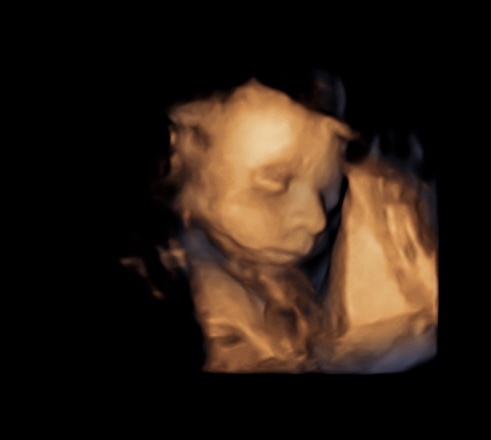

3D/4D ultrazvuk - tvárička drobca

Ahojte, kedy ste boli na 3D/4D ultrazvuku ? V ktorom TT ? Aby už pekne bola vidieť tvárička drobca ?

Ďakujem baby , nakoniec som si zavolala doktorovy a objednal ma na 26tt , vraj to je ideál že bude pekná babatkovska tvárička 😁 som zvedavá a už sa zas neviem dockat a budem škrkat v kalendári 💙😂🙋🏽♀️

@ki_ki2 ja prvy krat okolo 20tt to uz bola peknučkaa a potom okolo 28tt ale to uz bola moc velka tak sa schovavala